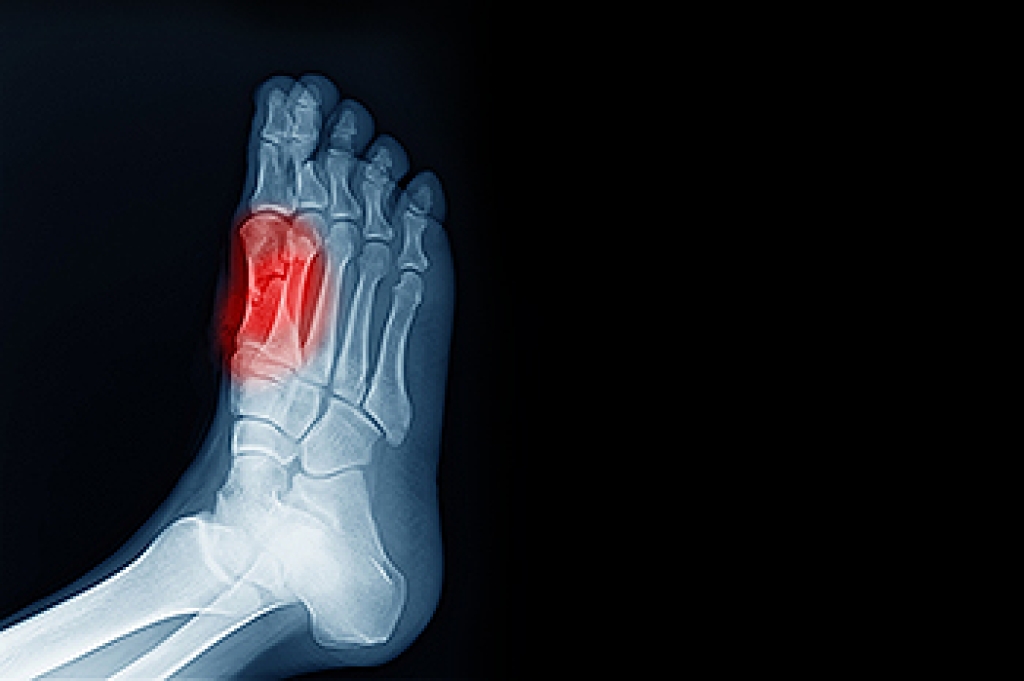

- Trauma to the toe, such as stubbing, which causes the nail to grow back irregularly